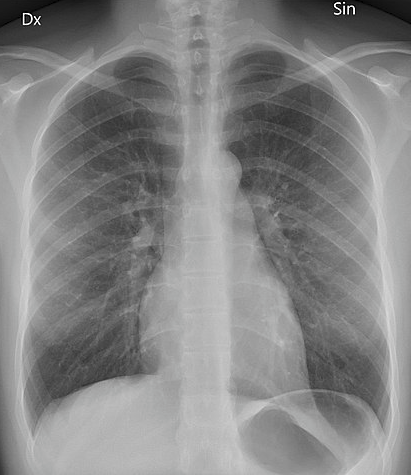

Back to contentsIn an X-ray picture bones show as light/white areas, whereas air shows as black or darker areas. The other lighter area in the middle of the image is the heart. The muscle which makes up the heart is also quite dense and stops X-rays passing through.

Posteroanterior chest X-ray

By Mikael Häggström (Own work) via Wikimedia Commons